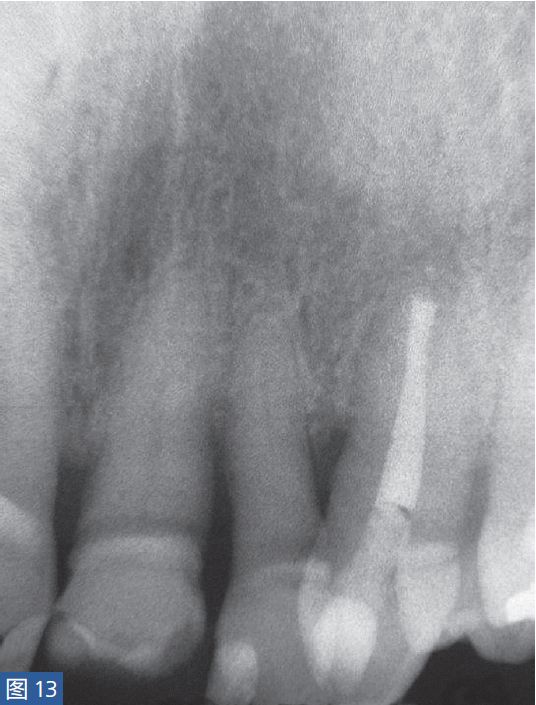

根尖周囊肿伴无症状性根尖周炎(AAP)根尖周囊肿(图12 和13)总是与无症状的根尖周炎相关。目前普遍认为,通过上皮残留细胞的炎性增殖形成了根尖周囊肿。在组织学上,它们分为袋囊肿和根尖周真性囊肿。通常认为,袋囊肿可以通过单纯的根管治疗而非手术方式,即通过细胞凋亡和程序性细胞死亡达到愈合。这种方式在真性囊肿似乎不太可能实现。

图12:23 牙齿根尖周囊肿 。非手术治疗,采取单纯的根管治疗后的X 线片检查。因未愈合而决定采取手术治疗。

图13:手术性根管治疗一年后的对照X 线片显示根尖病灶已愈合。对搔刮出的组织进行组织病理学检查显示为真性根尖周囊肿。